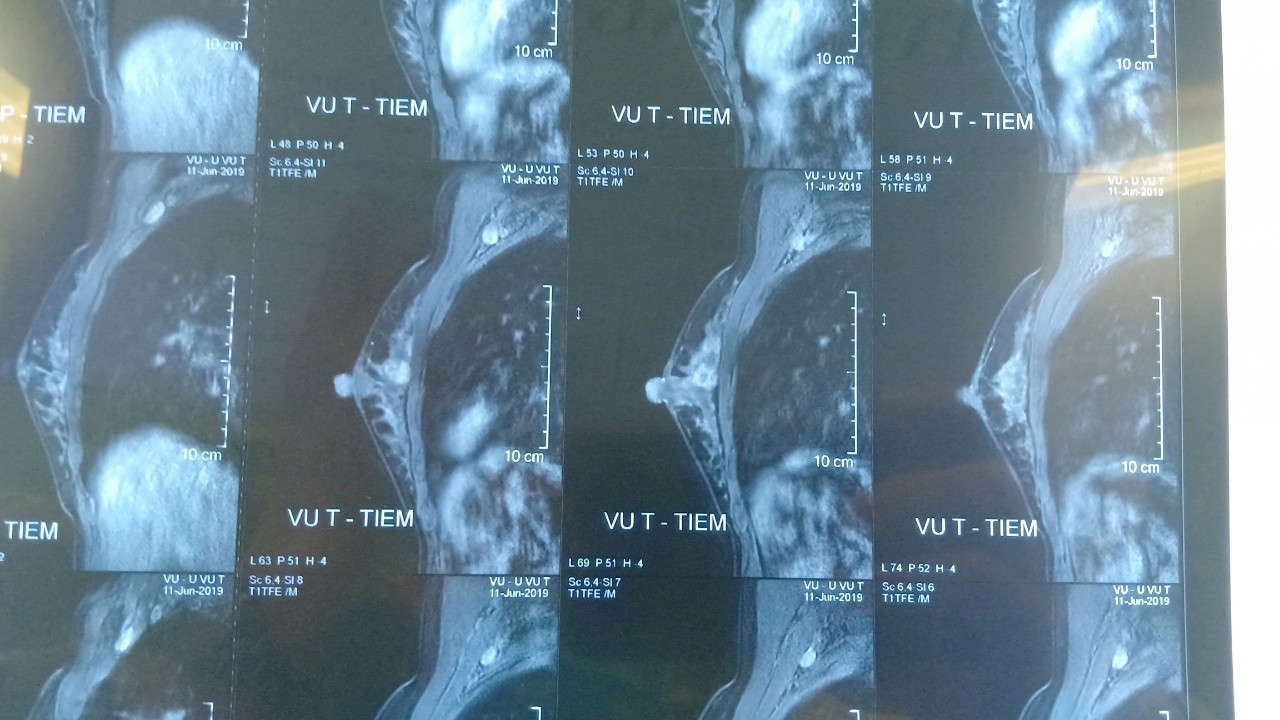

Hình ảnh phim chụp khối u của bệnh nhân trước khi phẫu thuật